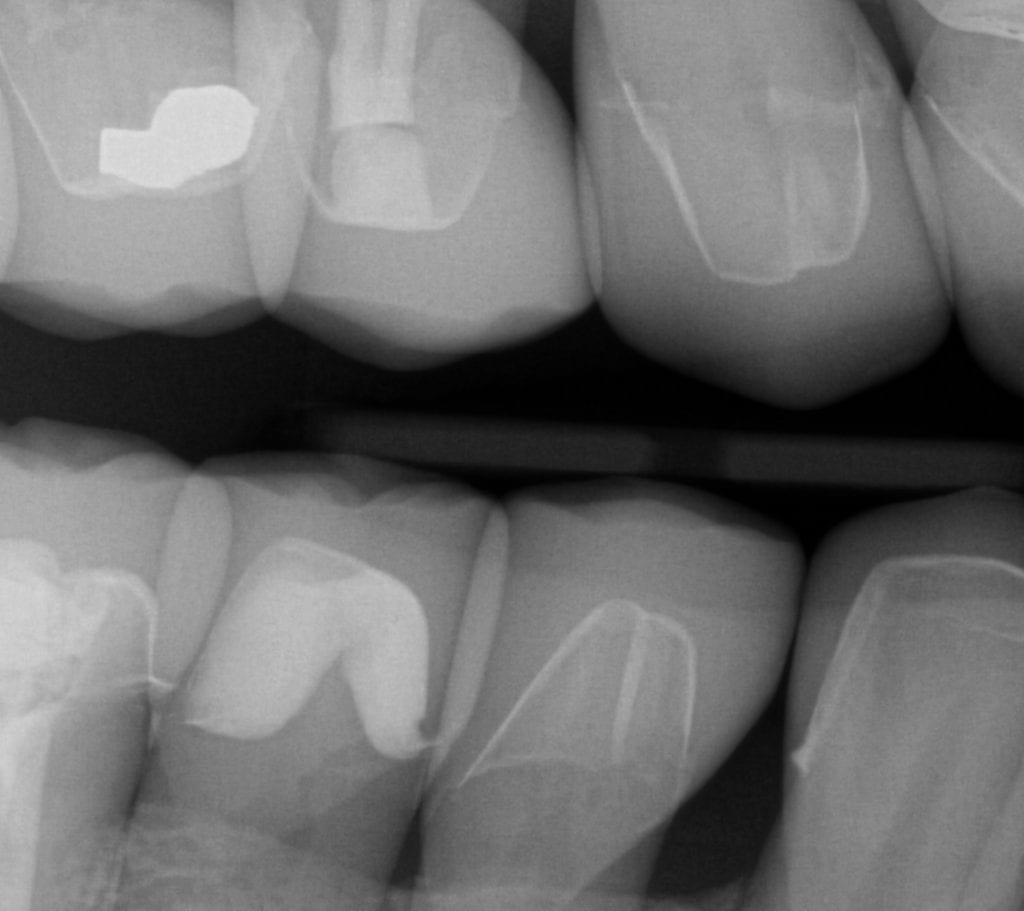

Pre-existing restorations that warranted replacement with an increase in vertical dimension.

Pre-existing restorations that warranted replacement with an increase in vertical dimension. The upper and lower arch were captured with the medit I500 and articulated together with enough clearance to accommodate new restorations and to restore the patient to an ideal tooth position.

ONE WEEK POST-OP RADIOGRAPHS / CEMENT CHECK